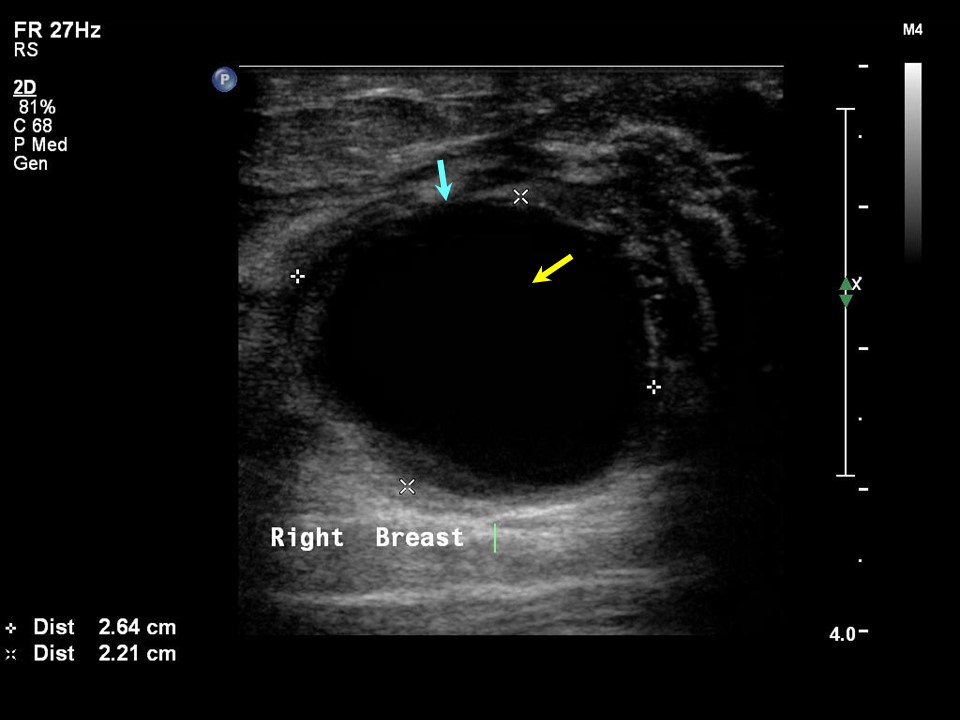

From www.researchgate.net

An ultrasound image of breast cyst. Download Scientific Diagram Painful Breast Cyst Mumsnet I went to the breast clinic. I also have an strange feeling in. When i first discovered my fibroadenoma it was painful. 2 months ago one of my breasts suddenly became painful and swollen and i thought i could feel a small lump. It’s a small lump on top of a larger lump on the outside of my right boob.. Painful Breast Cyst Mumsnet.

From ar.inspiredpencil.com

Breast Cyst Ultrasound Painful Breast Cyst Mumsnet They are one of the. Breast cysts are a benign (not cancer) condition. It’s a small lump on top of a larger lump on the outside of my right boob. I went to the breast clinic. 2 months ago one of my breasts suddenly became painful and swollen and i thought i could feel a small lump. Breast cysts, on. Painful Breast Cyst Mumsnet.